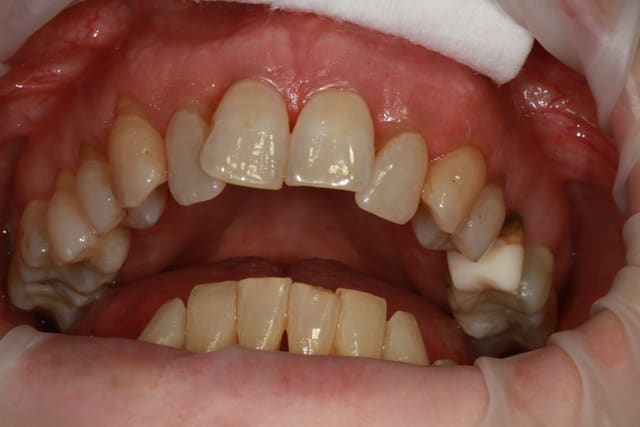

patiente 62 ans région Parisienne, appelle pour un avis, son praticien, paro, imlpanto etc... lui dit que sa paro n'a plus besoin de soin et propose pour les 6 antérieurs (j'ai le devis sous les yeux) 6 Inlay Core et 6 CCM...

Les panos sont du départ, les photos sont après un nettoyage ...profond et soins.